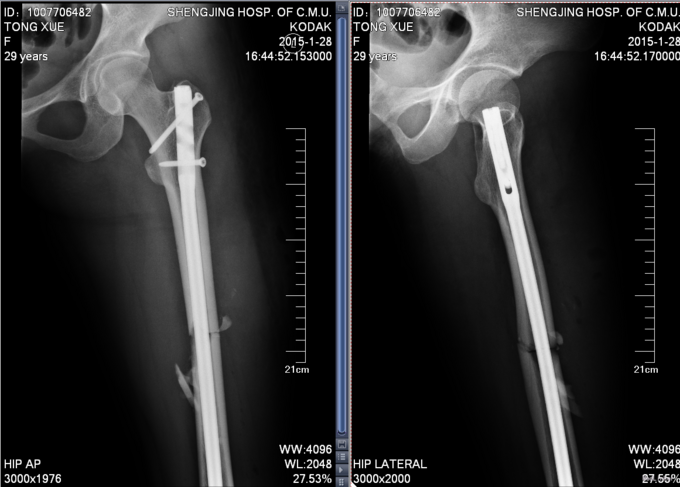

患者自述今日凌晨4点饮酒后意识模糊,后步行至某处天桥时,从天桥上摔落(因意识模糊原因未知),伤后知晓自己被送上救护车,伤后急送至我院急诊,于急诊处拍片检查示:左股骨干骨折、。后为进一步治疗转入我科,我科诊断为“左股骨干骨折”后收入,患者伤后无昏迷,无恶心呕吐,无呼吸困难,排尿正常,未排便。

专科查体:左下肢中段肿胀明显,压痛纵向叩击痛阳性,未触及骨擦音骨擦感及反常活,右下肢短缩长约3cm,左下肢感觉正常,左踝关节背伸及跖屈肌力5级,左足背动脉搏动有力,末梢血运良。

患者入院后完善检查后,急诊行左股骨干骨折闭合复位内固定术,术后患者卧床休息。患者生命体征平稳,术后一星期后出院。